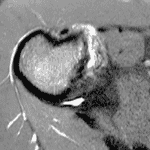

In this month's Radsource MRI Web Clinic, Dr. Neil Kennedy highlights the MRI and clinical features of a specific meniscal lesion seen in knees with torn anterior cruciate ligaments. These "ramp lesions" have important implications for subsequent knee stability.